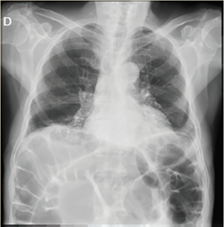

Paciente del sexo masculino, de 76 años, quien inició padecimiento actual hace 72 horas, con presencia de distensión y dolor abdominal opresivo 8/10 por “escala visual análoga” detonado por ingesta, sin presentar evacuaciones ni canalización de gases. Refirió tratamiento sintomático con antiespasmódicos, antiácidos y medicación local transrectal (supositorio), sin mejoría. Como antecedentes relevantes menciona patrón intestinal anormal con tendencia a la constipación crónica. A la exploración física dirigida, abdomen prominente a expensas de distensión de asas intestinales, peristaltismo disminuido con ruidos hidroaéreos, timpánico a la percusión con características metálicas, doloroso a la palpación superficial y media, con hiperalgesia e hiperbaralgesia, signo de rebote dudoso, tacto rectal con ámpula rectal vacía. Se realizaron radiografías posteroanterior de tórax y anteroposterior de abdomen identificando colon sigmoides redundante con aumento del patrón de distribución aérea, la cual ocasionó sobreposición de asas sobre el ángulo hepático y esplénico, presencia de material de residuo en íleon y colon ascendente, así como edema interesa (figura 1 y 2).

Figura 1 AP de tórax. Aumento del patrón de distribución aérea en marco colónico, sobreposición de asas sobre ángulo esplénico y hepático